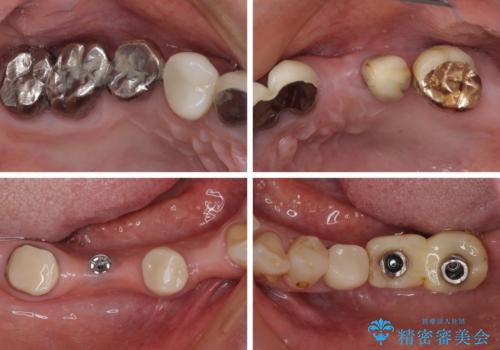

- 以前通院していた医院で、奥歯のインプラント埋入、前歯部のインビザライン矯正を行ったものの、そのまま放置してしまったとのことで来院された患者様です。

下顎前歯や上顎奥歯などをワイヤー装置により部分矯正を行い、歯列を整えた上でインプラン部分を含めてオールセラミッククラウンにて補綴治療を行うこととしました。

ご主人が通院されていたことで、ご紹介により来院されました。

インプラント上の仮歯がボロボロになり、前歯に非常に負担のかかる状態であったため、早急に奥歯の仮歯を修復し、矯正治療、奥歯の補綴治療、前歯の補綴治療と順々に進めて行きました。